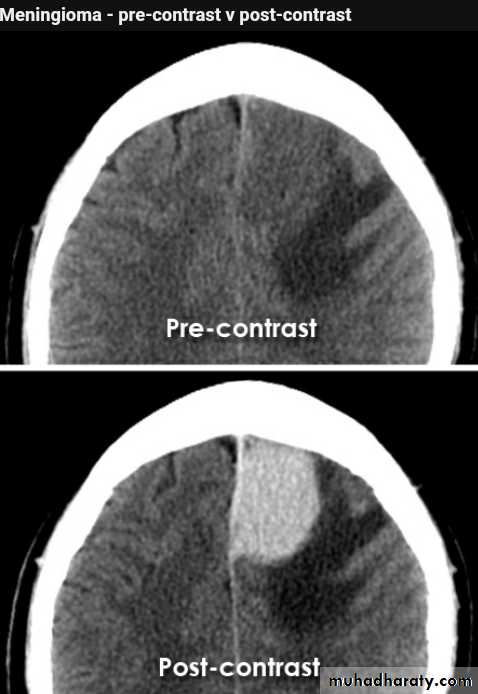

CT finding

meningioma presented as isodense area or slightly hyper density area with surrounded crescent of hypo density ( csf cap ) post contrast injection the lesion enhance homogeneously with enhancing Dural tail .